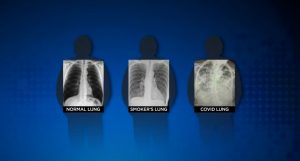

Nakon što je učestvovala u liječenju na hiljade oboljelih od Covid-19, hirurg dr. Brittany Bankhead-Kendall iz Teksasa, izjavila je da rendgenski snimci pluća pušača ukazuju na oštećenja, dok su pluća pacijenata koji su se borili sa koronavirusom na snimcima potpuno bijela.

„Ima ljudi koji kažu: 'Dobro sam, nemam nikakvih problema“, a kad im pogledate RTG grudnog koša, imaju jako lošu sliku pluća“, kaže doktorica koja je medijima pokazala tri rendgenska snimka: Jedan snimak zdravih pluća, jedan snimak pluća pušača i jedan snimak pacijenta koji je preležao Covid-19.

„Ne znam ko to treba da čuje, ali „post-covid“ pluća izgledaju gore od bilo koje vrste pušačkih pluća koja smo ikada vidjeli“, objavila je dr. Bankhead-Kendall na Twitteru početkom januara.

RTG snimak zdravog pacijenta pokazuje veliku količinu crnog prostora, što znači da je osoba u stanju da udiše veliku količinu vazduha. S druge strane, RTG pušača pokazuje bijele crte i maglovite mrlje, što ukazuje na upalu i oštećenje zidova pluća. Rendgen pluća osobe koja je preležala Covid-19 potpuno je bijel, kao da se nad njih nadvio bijeli oblak.

Takve promjene obično ukazuju na to da su pluća puna tečnosti, kao i bakterija. To takođe znači da pacijent nije u mogućnosti da unosi dovoljnu količinu kiseonika, što bi bilo moguće da su pluća zdrava.

„Pluća ili su prepuna bijelih gustih mrlja, ili se cijela pluća pretvore u bijeli oblak. Ako sad i ne osjećate probleme, RTG snimak pokazuje da biste ih vremenom mogli imati“, kaže doktorica za CBS DFW. Neki su pacijenti, dodaje, završili sa trajnim oštećenjima pluća ili ožiljcima, ali nije jasno da li to važi za sve pacijente.